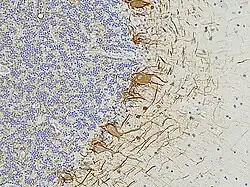

Numerous specific antibodies to neurofilament proteins have been developed and are commercially available. These antibodies can be used to detect neurofilament proteins in cells and tissues using immunofluorescence microscopy or immunohistochemistry. Such antibodies are widely used to identify neurons and their processes in histological sections and in tissue culture. The type VI intermediate filament protein Nestin is expressed in developing neurons and glia. Nestin is considered a marker of neuronal stem cells, and the presence of this protein is widely used to define neurogenesis. This protein is lost as development proceeds.

Neurofilament antibodies are also commonly used in diagnostic neuropathology. Staining with these antibodies can distinguish neurons (positive for neurofilament proteins) from glia (negative for neurofilament proteins).